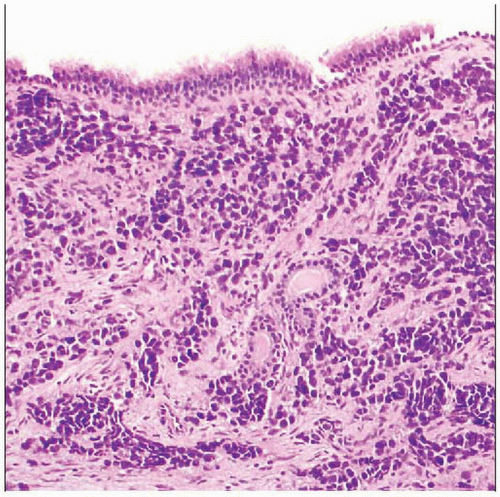

Alveolar Rhabdomyosarcoma | Basicmedical Key

basicmedicalkey.com

basicmedicalkey.com

rhabdomyosarcoma alveolar nests tissue infiltrated epithelium fibrous extensively overlies postnasal respiratory sheets seen space type